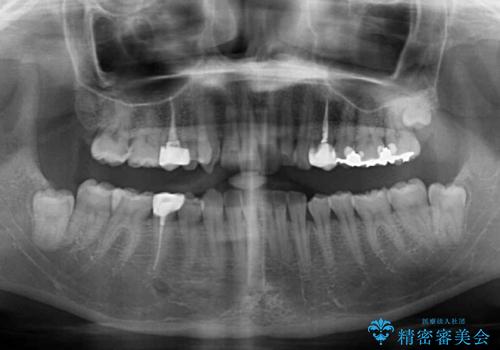

- 前歯の歯列不正を気にして来院された患者様です。

インビザラインでの矯正治療を希望されていましたが、奥歯の咬み合わせがインビザライン単独では改善困難と判断されたので、補助装置を併用することとしました。

まずは裏側の装置やワイヤー矯正を用いて歯列幅の狭い上顎を側方に拡大しつつ全体を後方に移動させ、その後インビザラインにて歯列を整えることとしました。